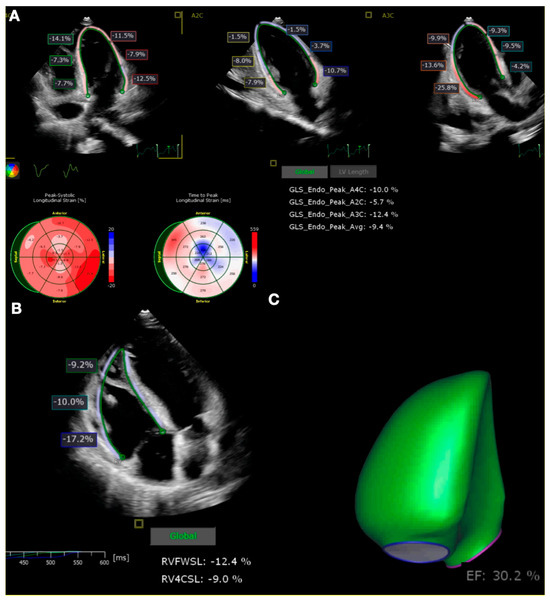

Abnormalities in the laboratory tests included the following: Troponin-I: 19,437 ng/L [N < 60 ng/L], NT-proBNP: 15,352 pg/mL [N < 125 pg/L], CRP: 17.8 mg/L [N < 10 mg/L], Lactates: 11.7 mmol/L [N < 1.6 mmol/L]. The next day, the patient’s condition deteriorated. Another echocardiography revealed a hypokinesis of the left ventricle, with an ejection fraction (LVEF) of 20%. Global longitudinal strain (GLS) of the left ventricle was −9.4%. Right ventricular dysfunction was observed, and the right ventricle ejection fraction (RVEF) was 30.2%. GLS of the free wall of the right ventricle was −9.0% (Figure 1). Subsequently, the patient developed respiratory failure, hemodynamic instability, liver failure and acute kidney injury, necessitating a transfer to the intensive care unit.

Figure 1. Global longitudinal strain assessment on transthoracic echocardiography. Global longitudinal strain of left ventricle on apical four-chamber, apical two-chamber, and three-chamber views (A), global longitudinal strain of right ventricle (B), and 3D reconstruction of right ventricle ejection fraction (C).